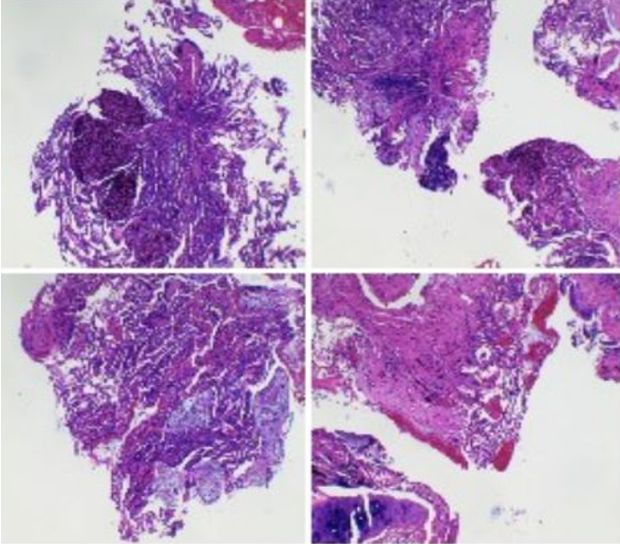

2月9日右侧胸膜结节病理学:镜下见增生间皮样细胞,急、慢性炎细胞浸润,较多嗜酸性粒细胞聚集,胶原化小结节形成(图7)。免疫组化结果支持为间皮增生,灶性呈乳头状增生,较多啫酸性粒细胞聚集、浸润,炎症重(图8)

图7  胸膜结节病理结果(2月9日)